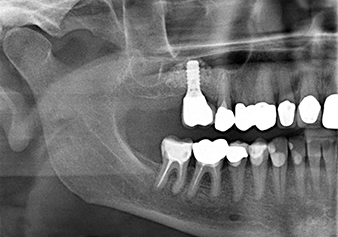

A 49-year-old female patient, a non-smoker and with nothing remarkable in her general medical history, was referred to our oral surgery practice for surgical extraction of tooth 16 and subsequent implantation. After the extraction, the patient experienced mild sinusitis trouble with the resultthat we initially waited six months before carrying out the measure. The residual bone height at the planned implant position measured 3-4 mm (Fig. 1 and 2).

Following an intermediate check (Fig. 4) a further preparation step was performed (Fig. 5). Afterwards, the hydraulic Z35P instrument was used to lift the membrane to the desired position (Fig. 6 and 7). This was followed by further piezosurgical preparation of the implant bed, concluded with a rotary bur and shoulder milling cutter up to the implant diameter of 4.8 mm. Before the implant was inserted, the augmentation material (particle size approx. 0.8-1.6 mm) was introduced underneath the Schneiderian membrane (Fig. 8).